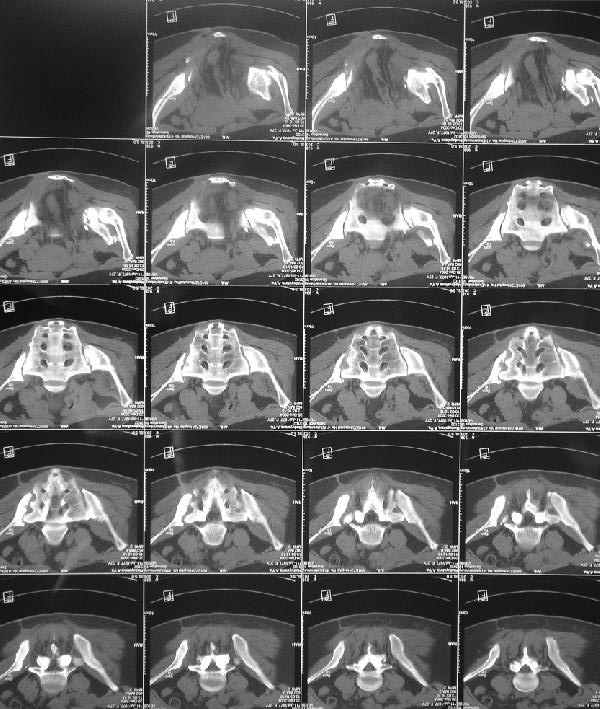

Снимки до лечения:

Картина на сегодня:

В настоящее время больная ходит без дополнительной опоры, боль в области таза не беспокоит, неудобств при сидении не испытывает, свободно проходит расстояние в 2-3км. Отмечается незначительная хромота, периодические боли в поясничной области низкой интенсивности, не требующие приема медикаментов, кроме того имеется вагинальный импинджемент. Срок после операции 1 год и 2 месяца. Было бы интересно услышать ваши комментарии. С уважением Агалаков М.В.